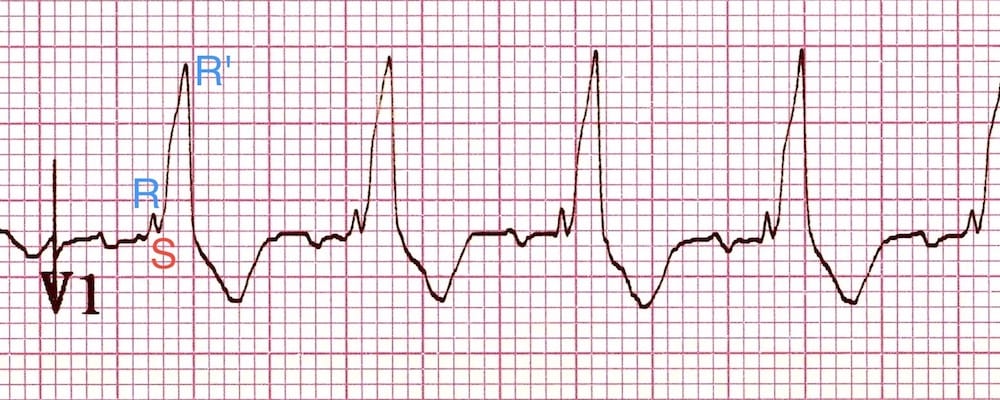

V1: RSR’ pattern in V1, with (appropriate) discordant T wave changes

QRS Morphology in V1

Sometimes rather than an RSR’ pattern in V1, there may be a broad monophasic R wave or a qR complex.

- RSR’ pattern in V1-3 (“M-shaped” QRS complex)

- Wide, slurred S wave in lateral leads (I, aVL, V5-6)